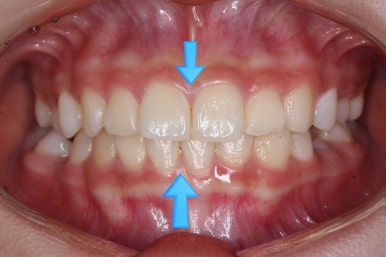

다만, 웃을 때 모습만을 보면 위아래 치아의 중앙이 서로 어긋나 있는 것을 볼 수 있습니다.

부산치아교정잘하는곳 처음 오셨을 때의 입안 모습입니다.

맨 우측 밑에 사진을 보시면 이가 하나 더 나와야 할 자리에(화살표) 앞뒤로 치아가 쓰러지면서 자리를 거의 없애버렸습니다.

왼쪽 맨 위 사진을 보시면 아래 치열의 중앙이 한 쪽으로 쏠린 것을 알 수 있는데요. 역시 치아가 나올 자리가 없어지면서 치열이 쏠러버렸다는 것을 알 수 있습니다.